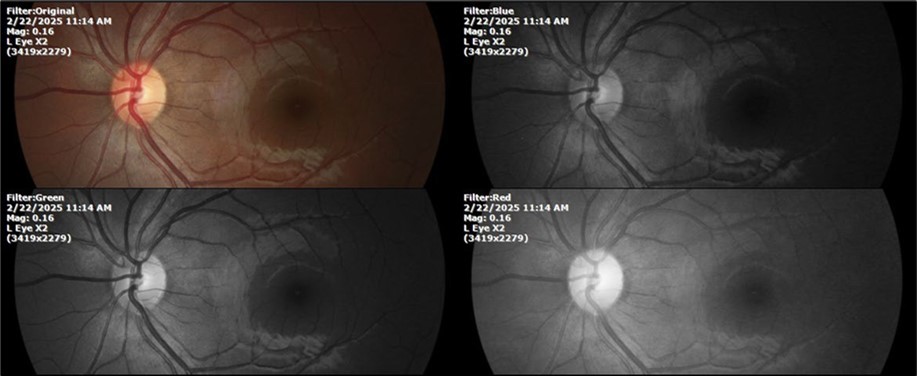

February 22, 2025

There is no pain, only minimal discomfort, and my vision has improved (Figure 20, Figure 21, Figure 22, Figure 23, Figure 24)

Figure 24.The eye that was not affected by the trauma (left side) remains in good condition.

The eye that was not affected by the trauma (left side) remains in good condition.